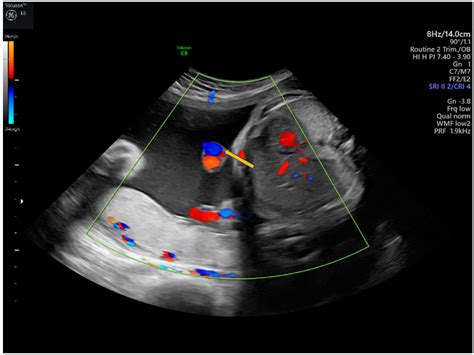

Diagnosis of Cord Knots

Cord knots are typically diagnosed through prenatal ultrasounds. During a routine ultrasound, the healthcare provider can visualize the umbilical cord and identify any knots or abnormalities. In some cases, additional tests such as a non-stress test (NST) or biophysical profile (BPP) may be recommended to assess the baby's well-being.